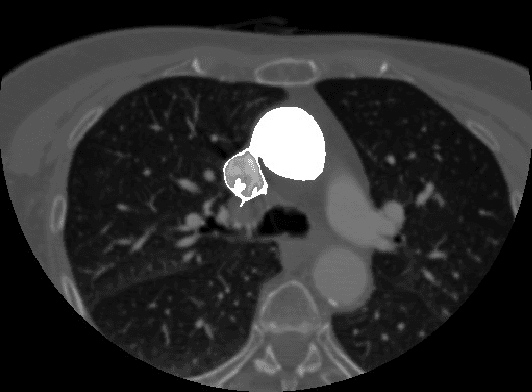

Segmentation of medical images using seeded region growing technique is increasingly becoming a popular method because of its ability to involve high-level knowledge of anatomical structures in seed selection process. Region based segmentation of medical images are widely used in varied clinical applications like visualization, bone detection, tumor detection and unsupervised image retrieval in clinical databases. As medical images are mostly fuzzy in nature, segmenting regions based intensity is the most challenging task. In this paper, we discuss about popular seeded region grow methodology used for segmenting anatomical structures in CT Angiography images. We have proposed a gradient based homogeneity criteria to control the region grow process while segmenting CTA images.